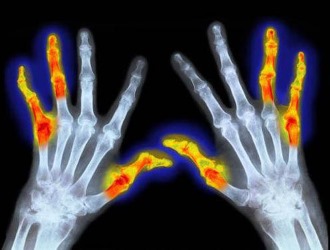

| Показания к применению | Ревматоидный артрит, остеоартроз, анкилозирующий спондилит, подагра, боли в спине, травмы | Широкий спектр применения при различных болевых синдромах |

Показания

Представляем вашему вниманию расширенный перечень показаний для использования Тексамена.

Данное лекарственное средство рекомендуется при наличии следующих заболеваний:

- Артрит;

- Подагра;

- Остеоартроз;

- Спондилит;

- Остеохондроз;

- Тендинит;

- Люмбаго;

- Невралгия;

- Миалгия;

- Миозит;

- Периартрит;

- Бурсит;

- Головная боль;

- Ожоги;

- Ишиалгия;

- Зубная боль.